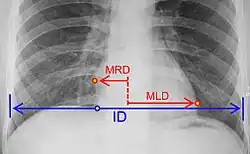

where:[29]

MRD = greatest perpendicular diameter from midline to right heart border

MLD = greatest perpendicular diameter from midline to left heart border

ID = internal diameter of chest at level of right hemidiaphragm

- Chest X-ray: X-ray images help to visualize the condition of the lungs and heart. If the heart is enlarged on an X-ray, other tests will usually be needed to find the cause. A useful measurement on X-ray is the cardio-thoracic ratio, which is the transverse diameter of the heart, compared with that of the thoracic cage.[30] These diameters are taken from PA chest x-rays using the widest point of the chest and measuring as far as the lung pleura, rather than lateral skin margins. If the ratio is greater than 50%, pathology is suspected.[31] The measurement was first proposed in 1919 to screen military recruits. A newer approach to using these x-rays for evaluating heart health takes the ratio of heart area to chest area and has been called the two-dimensional cardiothoracic ratio.[32]